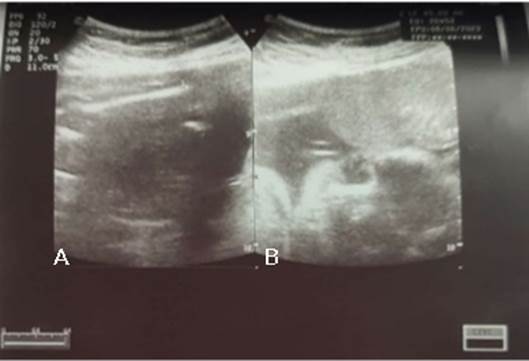

Figura 1 Reporte ecográfico de la paciente a las 23 semanas de gestación (07/03/2023): A: Corte sagital fetal, se observa la longitud total del fémur fetal. B: Corte coronal de la cara fetal, donde se evidencia placenta de inserción baja en cara anterior: donde se visualiza pérdida de la clear zone (plano hipoecogenico retroplacentario), así mismo no se visualiza miometrio retroplacentario.